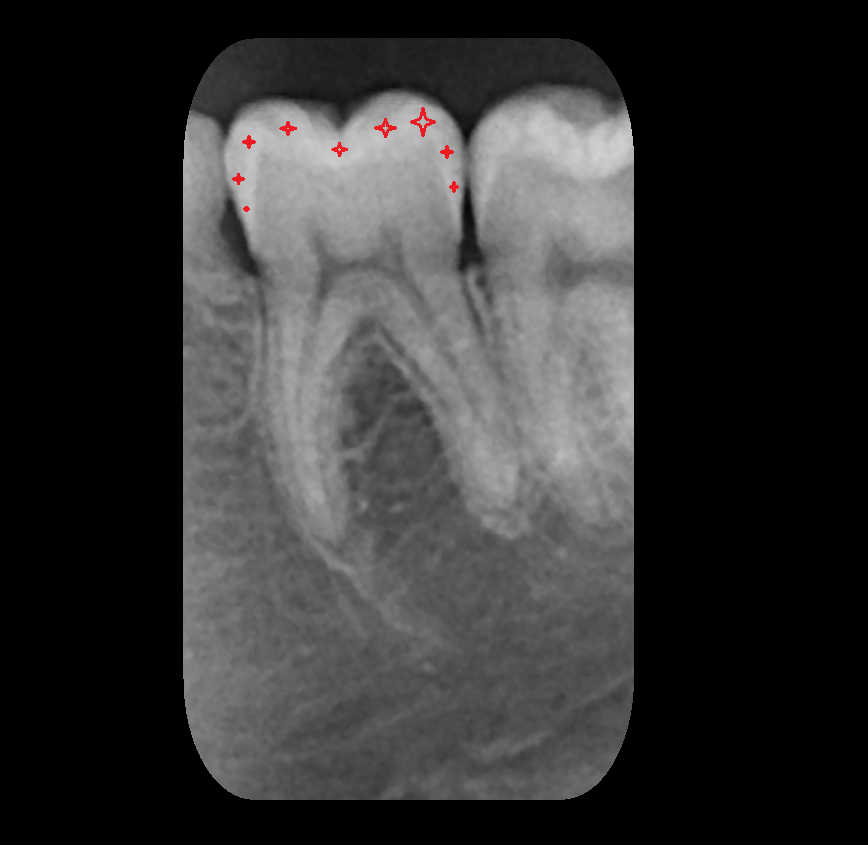

- Root of lower molar tooth

- Lower molar apical foramen

- Upper premolar apical foramen

- Root of upper molar tooth

- Root canal of upper molar tooth

- Dental pulp of upper molar tooth

- Enamel of lower molar tooth

- Enamel of upper molar tooth

- Dental pulp of lower molar tooth